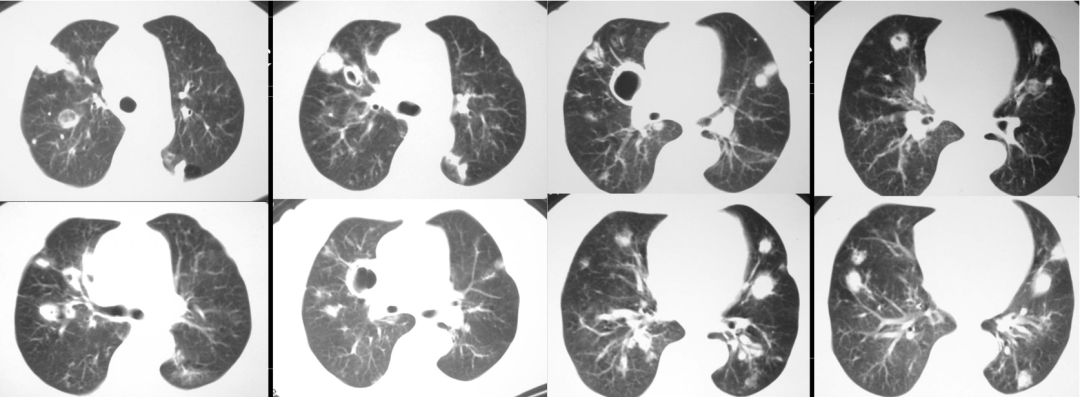

不怪我会如此担心。对于普通人来说,吃饭呛一下没什么大不了。但年过七十的云阿姨身患淋巴瘤,在外院治疗时,还出现了肺空洞(图1),痰中有曲霉菌。经过几次化疗,她的身体已经非常虚弱,合并有心功能衰竭。若是因呛咳诱发肺炎,造成心衰加重,那真是「雪上加霜」!

图1.胸部CT显示云阿姨肺内多发结节及空洞改变